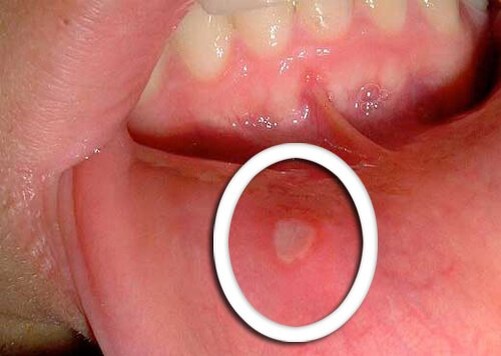

Афты — это небольшие язвы во рту, их появление может вызвать серьезный дискомфорт. Хотя они могут быть очень маленьким, но болят и раздражают. Почему афты появляются в ротовой полости? Очень часто бывает так, что мы не знаем, почему появляются эти инфекции. Эксперты также не могут точно определить причину их появления, хотя эта проблема затрагивает около 20% нашего населения, вызывая боль и дискомфорт, как при разговоре, так и при еде. Афты могут встречаться в двух формах: простых и сложных. Первые случаются несколько раз в год и длятся максимум неделю, чаще всего это затрагивает людей в возрасте от 10 до 20 лет. Афты во рту могут появляться по разным причинам. Их может вызвать стресс, употребление кислых блюд или цитрусовых, ослабление иммунной системы, проблемы с питанием или заболевания пищеварительной системы. Важно различать язвы во рту, известные как афты, от герпеса, ведь они могут выглядеть одинаково, но у них совершенно разные причины. Герпес вызван простым вирусом и являетс

Симптомами язв в полости рта являются: жжение, болезненное покалывание, круглые раны белого или серого цвета с покраснением по краям, лихорадка, опухание лимфатических узлов и т. д. Хорошая новость заключается в том, что афты почти всегда исчезают сами по себе. Боль во время появления язвы очень раздражает, поэтому очень важно не поддаваться соблазну временного облегчения и не трогать проблемные места. Через семь или десять дней они должны исчезнуть.